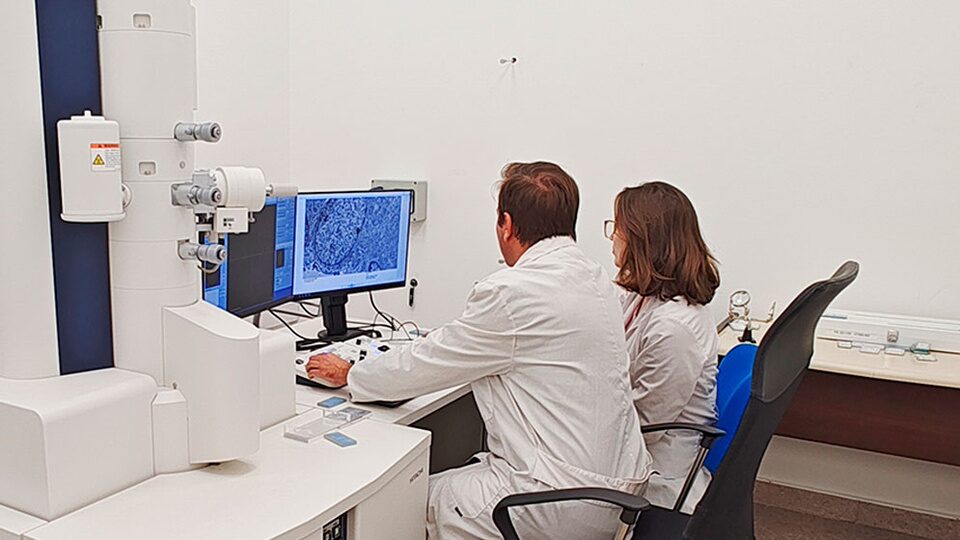

Células tumorales de pacientes con tumor somatotropo observadas mediante microscopio electrónico de transmisión. (Imagen: Conicet)

Juan Pablo Petiti, investigador del CONICET, y Gilda Mezger, becaria del CONICET, analizando células tumorales en un microscopio de alta resolución.